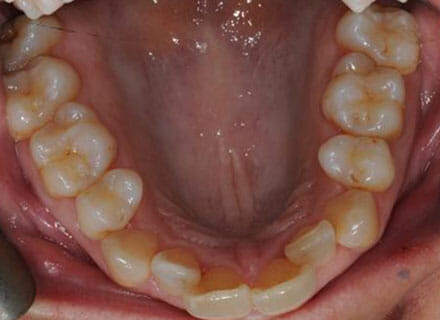

In this case, we needed to reduce the size of the central incisors as they were just too big. This combined with the crowding at the front had caused the lateral incisors to become trapped inside, pushing the big central incisor teeth forwards even more. After reducing the big teeth to a normal size we started with fixed clear bracket brace treatment and were able to complete this case in a little over a year.